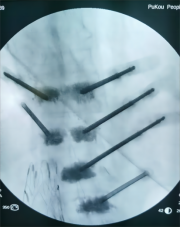

5.微创胸腰椎固定融合技术

微创胸腰椎固定融合技术适用于治疗腰椎间盘突出症、腰椎管狭窄症、腰椎失稳、腰椎滑脱、胸腰椎骨折、腰椎峡部不连及部分翻修手术等。其与传统TLIF技术相比,该技术通过最小的创伤即能达到和开放腰椎减压融合手术同样的临床效果,同时可减少并发症,实现病人快速康复的目的。